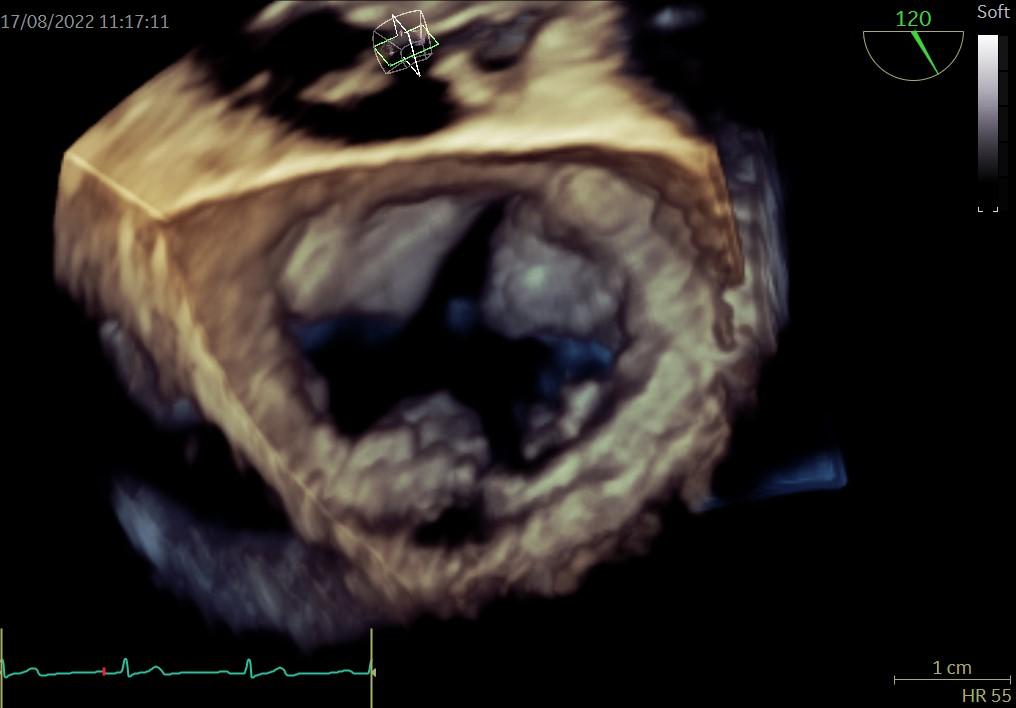

Uprzejmie informujemy, iż na stronie internetowej Asocjacji w sekcji WADY SERCA W OBRAZACH umieśliśmy nowy przypadek: Rozszczep przedniego płatka mitralnego.